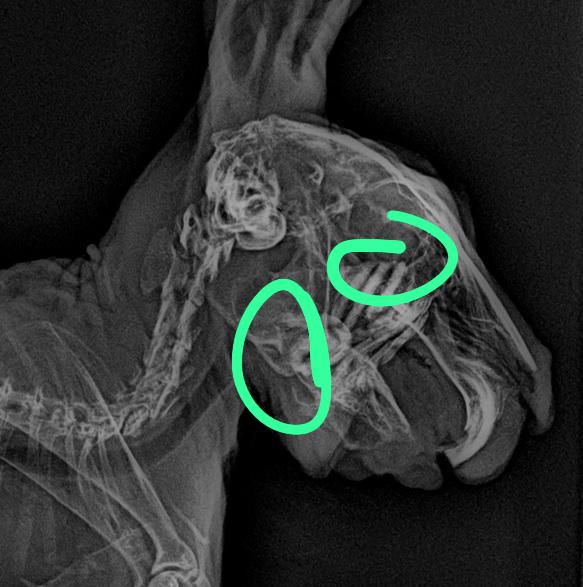

門牙感染、充滿膿液

牙根過長(食物太過多樣化、兔兔挑食誘發只食甜食,拒食硬草)

2. 影像檢查:X 光可評估腸道氣體、糞塊位置和牙齒結構;或需鎮靜。

• 牙科問題:在麻醉下修整牙齒,移除尖刺,或處理牙根膿腫。術後需服用止痛及抗生素。